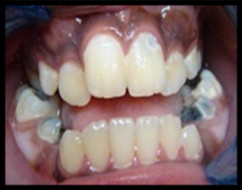

He encontrado un artículo de estudio de caso bastante interesante de A. Al-Jobair del Departamento de Odontología Pediátrica y Ortodoncia de la Facultad de Odontología de la Universidad Rey Saud, publicado en 2010. De este artículo destacaré sus partes más importantes. Este es un estudio de caso de una niña de 11 años de edad.

"La paciente parecía ser bien integrada, se la veía sana e inteligente, pero tenía dificultad para hablar. En su visita inicial tenía un tamaño de 100 cm de estatura. El examen extraoral reveló manifestaciones clásicas asociadas con la acondroplasia como ser: baja estatura, manos cortas y en tridente, prominencia frontal, puente nasal hundido, hipoplasia severa de la cara media y labios incompetentes. Se observó respiración bucal, brecha interlabial de aproximadamente 12 mm en reposo y una mente hiperactiva. El cierre de los labios no fue posible sin tensión muscular. También fue observado un perfil facial cóncavo, sin embargo, la mandíbula parecía normal y la barbilla no era prominente."

Intraoralmente, se observó macroglosia  un patrón de deglución con empuje de la lengua, gingivitis generalizada, mordida cruzada posterior, mordida abierta anterior (igual que la maloclusión) y una reacción invertida anterior. Había una relación molar dental clase III con apiñamiento (una de las complicaciones dentales más comunes en pacientes acondroplásicos) en la región maxilar anterior. La paciente tenía dentición mixta: tamaño, número y forma de los dientes era normal con múltiples lesiones y restauraciones de caries. La erupción de los dientes era compatible con la edad cronológica. La radiografía panorámica mostró un número completo de dientes permanentes, incluyendo terceros molares con desarrollo normal, apiñamiento en las regiones caninas y en los molares superiores. El análisis cefalométrico de la radiografía lateral del cráneo reveló que el maxilar era severamente retrognático (posición anormal del maxilar, cuando empuja hacia atrás, con relación al esqueleto facial y a los tejidos blandos), con la posición normal de la mandíbula, con la altura facial superior disminuida, con la altura facial inferior aumentada y con una relación esquelética de mandíbula de clase III. Dentalmente, los incisivos maxilares estaban reclinados y los incisivos mandibulares estaban normalmente inclinados. Se evaluó el riesgo de caries. El plan de tratamiento fue formulado tanto para extraer todos los dientes primarios cariados como para restaurar todos los dientes permanentes cariados. Se realizó el tratamiento dental según lo planificado, con anestesia local y la colaboración de la paciente. Esta fue colocada en un programa de visita al odontólogo a cada tres meses.

gr4 gr6 gr7